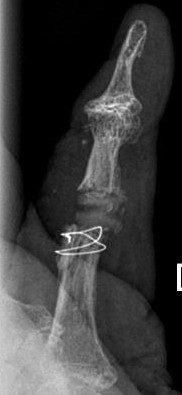

Blickfang ist hier das x-förmige Implantat zur Versteifung eines schmerzhaften und ehemals deformierten Endgelenkes.

Im Mittelgelenk fällt ein flauer "Schatten" von einem Kunstgelenk aus Silikon (Silikonendoprothese) auf.

14 Jahre nach Implatation einer Pyrrocarbon Endoprothese ist es hier zur vollständigen knöchernen Überbauung gekommen Rechts das postoperative Bild mit Entfernung des Knochens, der Prothese und Einbau eines Silikonspacers. Ein Draht sichert die Knochenschuppe, die Zur Entfernung abgehoben wurde. |